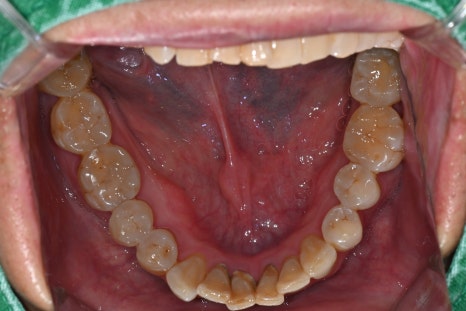

▼ 아래는 본원에서 치료한 실제 스케일링 전후 사진입니다.

-치료 전

오른쪽 사진: 전체적으로 잇몸이 부어있습니다. 특히 아래 앞니쪽에 치석이 다량으로 쌓여있어 잇몸 염증을 유발하는 상태입니다.

- 치료 후

오른쪽 사진: 치석이 제일 많았던 아래 앞니 사진 입니다. 치석 제거후 깨끗해진 상태입니다.